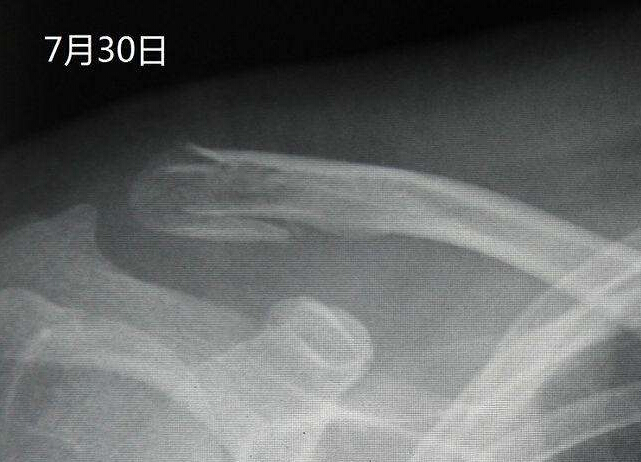

【摘要】通过拍摄X线片,可以了解骨折的部位,骨折线的走向,骨折的移位情况,骨折的类型等,为医师制定治疗方案,监测治疗结果提供依据。X线照片一般需要拍摄正位和侧位,同时应包括邻近关节,这样才能全面地反映出骨折的全貌。尽管如此,有些骨折还需要加摄特定位置才能显示骨折线,有些骨折需经1~2周后骨折处骨质吸收才能显示骨折线。

通过拍摄X线片,可以了解骨折的部位,骨折线的走向,骨折的移位情况,骨折的类型等,为医师制定治疗方案,监测治疗结果提供依据。X线照片一般需要拍摄正位和侧位,同时应包括邻近关节,这样才能全面地反映出骨折的全貌。尽管如此,有些骨折还需要加摄特定位置才能显示骨折线,有些骨折需经1~2周后骨折处骨质吸收才能显示骨折线